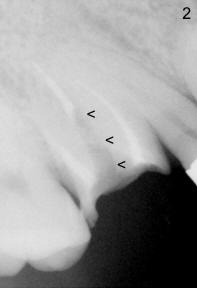

1. A post is needed when the tooth has a large defect and has finished root canal therapy (R in Fig.1).  There are two types of post: prefabricated and cast (one and two appointments, for small and large decays, respectively).  A post space is created in the largest canal of the tooth (arrowheads in Fig.2).  Either a prefabricated post is inserted into the post space or a plastic pattern is made to fit the space.  The outside portion of the pattern is prepared (trimmed) to become part of the tooth structure.  The plastic pattern is sent to lab to make a cast post (P) and core (C, Fig.3), which is inserted (Fig.4) into the post space.  Finally a crown is cemented (Cr in Fig.5)

3. PA device is needed for both appointments: to confirm length of post space to be created (Fig.2) and seating of cast post (Fig.4)